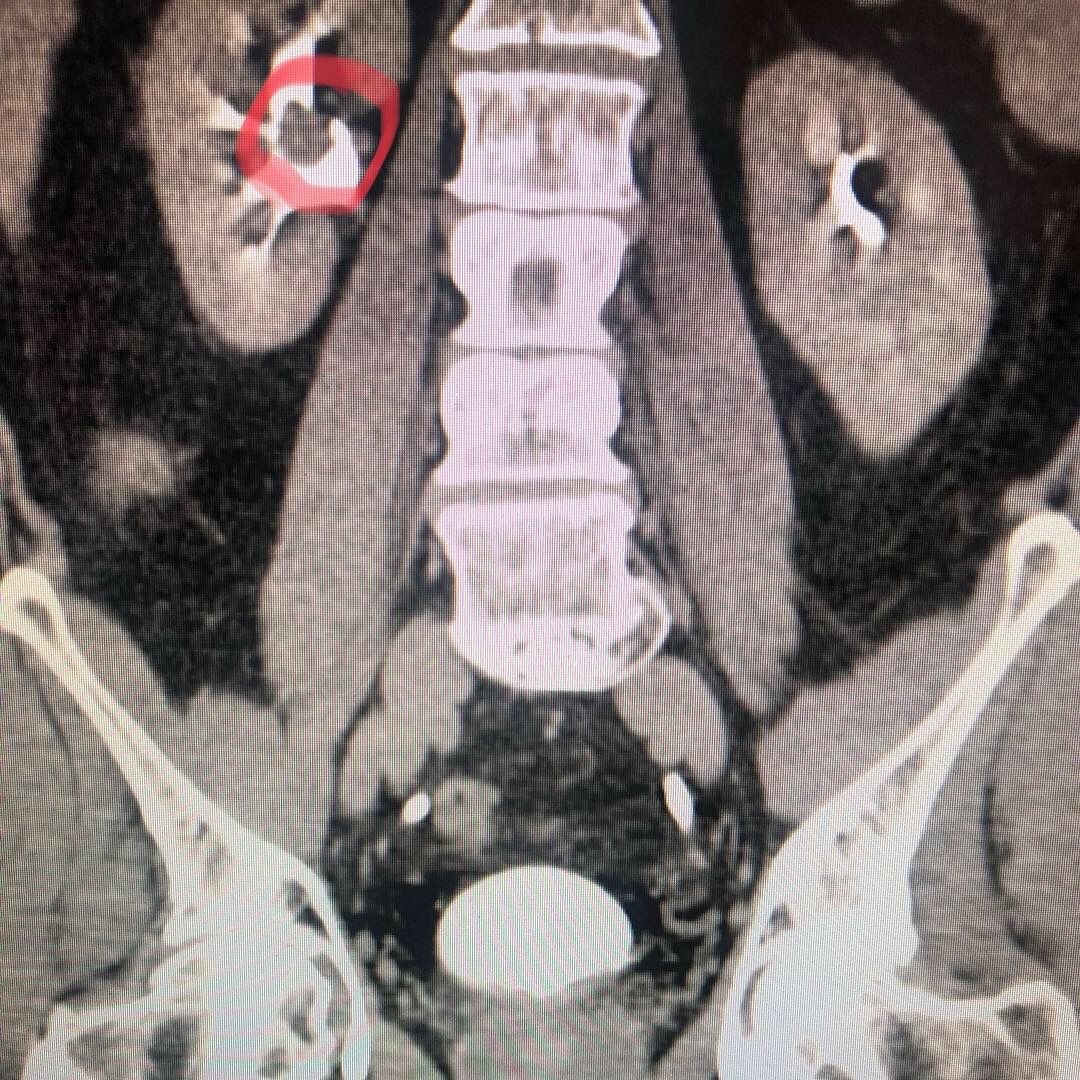

Resultados obtenidos con nefrolitotomía percutánea y su correlación con las escalas de Guy y S.T.O.N.E. en un hospital de la Ciudad de México.Revista Mexicana de Urología 2016;76:203-6

Cirugía de cálculo ureteral

Es un procedimiento que se hace por medio de endoscopia (ureteroscopia) de la via urinaria, en donde se entra al ureter a través de la vejiga, se llega hasta el sitio donde se encuentra el calculo o líto urinario que esta obstruyendo parcial o totalmente la luz del uretero. Con instrumentos muy delgados se fragmenta el líto con rayo laser y sus arenillas o fragmentos son extraidos por medio de una canastilla especial. una vez extraido el calculo su medico valorara la colocación de un cateter doble J, con la finalidad de mantener abierto el consucto del ureter durante un par de semanas y posterior a ello se retira el cateter. Existen otras técnicas de tratamiento, cada caso debe personalizado.